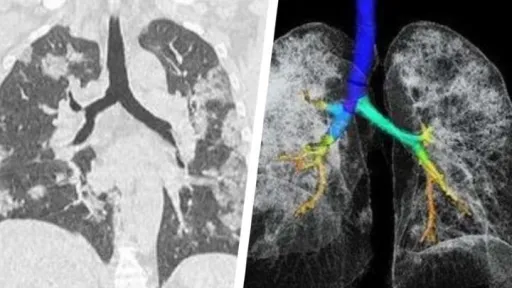

Mai multe studii arată că persoanele contaminate cu noul coronavirus ar putea rămâne cu probleme pulmonare pentru tot restul vieţii. Primele avertizări în acest sens au venit din China, în luna martie, când pandemia abia începea în Europa.

Un studiu relativ mic raporta că din 70 de pacienți care au dezvoltat pneumonie 66 au rămas cu leziuni pulmonare. Aceste leziuni se manifestau în moduri diferite de la pacient la pacient și păreau să afecteze fie alveolele pulmonare, fie țesuturile din jurul alveolelor.Un alt studiu din Hong Kong descria cum, din 20 de pacienți internați pentru Covid-19, jumătate nu și-a recăpătat în totalitate funcția pulmonară.Mai mult, în vreme ce SARS și MERS (coronavirusuri înrudite cu virusul care cauzează COVID-19) păreau să afecteze un singur plămân, aici ambii plămâni erau afectați.Yuhui Wang, unul dintre autorii studiului din China, menționa că se așteaptă ca o parte din aceste leziuni să se vindece în timp, dar nu a trecut suficient de mult timp pentru a avea o certitudine în această direcție.Cea mai mare problemă este că o parte a leziunilor par a fi permanente, în special cele cauzate de cicatrizarea țesutului pulmonar. Un răspuns prea puternic al sistemului imunitar (așa-numita furtună de citokine) ar cauza aceste leziuni. Cei care sunt în special expuși acestei probleme sunt cei mai în vârstă sau cu probleme preexistente de sănătate.Totodată, într-un interviu acordat ziarului olandez AD și tradus de NLTimes, pneumologul Leon van den Toorn spunea că "mii de olandezi ar putea avea leziuni pulmonare permanente" cauzate de COVID-19.Conform lui van den Toorn, dintre cei 1.200 de pacienți care au fost internați la terapie intensivă, peste 100 au plecat acasă cu leziuni. De asemenea, adaugă doctorul olandez, cam jumătate din cei 6.000 de oameni care au fost spitalizați vor rămâne cu simptome pulmonare ani în șir.Aceste simptome includ dificultăți sporite în respirație, în special la depunerea de eforturi ușoare, care, în mod normal, nu ar cauza probleme. Pot indica probleme remanente și pot duce la scăderea oxigenării sângelui, care ar putea cauza alte probleme de sănătate. Medicii din Marea Britanie au tras concluzii similare, atrăgând atenția că mulți pacienți de COVID-19 ies din spital cu probleme pulmonare.Ce trebuie să știm?Nu e deloc surprinzător că această infecție cauzează probleme cronice pentru supraviețuitori. În cazul MERS, peste o treime din cei care au avut probleme pulmonare nu-și reveniseră nici după câteva luni, iar probleme similare au fost raportate și la SARS.Pentru cei care au avut această boală – și pentru doctorii care i-au supervizat – este important să monitorizeze apariția acestor simptome. Pacienții pot nota simptomele observate, iar într-un cadru medical se pot face radiografii pentru a confirma potențialele leziuni.Doctorii olandezi au lansat deja o platformă prin care vor să urmărească evoluția problemelor cronice pulmonare apărute ca urmare a infecției cu noul coronavirus și e un model pe care am putea să-l urmăm.Pentru noi toți, e un semnal de alarmă: de multe ori ne uităm la o boală și la câți oameni omoară, dar ignorăm suferința mai amplă provocată din cauza bolii.sursa: www.libertatea.ro